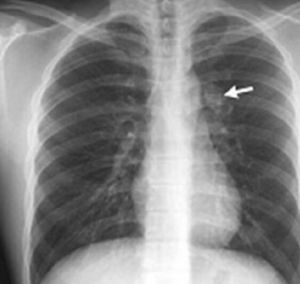

基本信息 中文名: 肺部腫瘤 外文名: lung tumor 傳染病: 否 臨床表現: 吸菸、職業致癌因子、空氣污染等 就診科室: 腫瘤科 發病部位: 肺部 常見症狀: 發熱、咳嗽、咯血、肺部感染能否治癒: 可以治癒 病因及常見疾病 肺部腫瘤 一般認為肺癌(腫瘤)的發病與下列因素有關:吸菸、職業致癌因子、空氣污染、電離輻射。此外,病毒的感染、真菌毒素(黃霉曲菌)、結核的瘢痕、機體免疫功能的低落、內分泌失調以及家族 遺傳等因素對肺部腫瘤的發生可能也起一定的綜合作用。鑑別診斷 錯構瘤 位於肺部周圍,系由纖維組織,脂肪,支氣管 上皮和軟骨組成之良性腫瘤。圓形,直徑達1cm左右,有包膜,常含較多軟骨組織,故有時稱軟骨瘤。組織細胞瘤 又稱漿細胞肉芽瘤,腫塊直徑約2~5cm,最大為10cm,位於肺組織內,與肺 實質粘連較緊,位於肺表面者可與胸壁或膈肌粘連。組織學似慢性炎症,有大量漿細胞、組織細胞 。有時出現肺部感染症狀,如發熱、咳嗽、咯血,而診斷為肺炎或肺葉不張。此瘤發生於肺外,有惡化傾向;於肺內屬良性,可切除腫塊與部分周圍組織。支氣管腺瘤 腫瘤生長較慢,為低度惡性。表面粉紅色,易出血,向支氣管腔內凸出,基底向管壁浸潤擴展,使腫塊大部於管壁,不能從支氣管鏡清除。腺瘤阻塞支氣管 後有反覆咳嗽、哮喘、咯血和肺部感染。肉瘤 肺肉瘤較多,有神經纖維肉瘤、平滑肌肉瘤、纖維肉瘤、橫紋肌肉瘤等。常因支氣管腔阻塞或腔外壓迫引起反覆咳嗽、發熱、咯血。檢查 (一)X線檢查: 通過X線檢查可以了解肺部腫瘤的部位和大小,可能看到由於支氣管阻塞引起的局部肺氣腫、肺不張或病灶鄰近部位的浸潤性病變或肺部炎變。 (二)支氣管鏡檢查: 通過支氣管鏡可直接窺察支氣管內膜及管腔的病變情況。可採取腫瘤組織供病理檢查,或吸取支氣管分泌物作細胞 學檢查,以明確診斷和判定組織學類型。 (三)細胞學檢查: 痰細胞學檢查是肺部腫瘤普查和診斷的一種簡便有效的方法。治療原則 手術治療 電視胸腔鏡肺葉切除術已成為早期肺部腫瘤的成熟療法之一,近、遠期療效與傳統開胸手術相當,但前者在降低創傷性方面具有顯著優勢。既往電視 胸腔鏡肺葉切除術主要用於治療腫瘤直徑≤5cm的肺部腫瘤,原因在於腫瘤占位小,容易翻動肺組織,對肺門、葉間裂血管的影響小,且操作較為方便。對於腫瘤直徑>5cm的肺部腫瘤而言,腫瘤占位明顯,難以翻動肺組織,電視胸腔鏡下的術野狹窄,全鏡下切除、取出的難度顯著增大。近年來,隨著電視胸腔鏡肺葉切除術的成熟、發展,腫瘤直徑>5cm的肺部腫瘤已不再作為該術的禁忌證,但在治療過程中仍需要考慮手術 安全性、徹底性和有效性。放射治療 放療對小細胞 肺癌療效最佳,鱗狀細胞癌次之,腺癌最差。肺癌放療照射野應包括原發灶、淋巴結轉移的縱隔區。同時要輔以藥物治療。鱗狀細胞癌對射線有中等度的敏感性,病變以局部侵犯為主,轉移相對較慢,故多用根治治療。腺癌對射線敏感性差,且容易血道轉移,故較少採用單純放射治療。化學治療 化療一般不能治癒非小細胞肺癌,只能延長患者生存和改善生活質量。化療分為治療性化療和輔助性化療。化療需根據肺癌組織學類型不同選用不同的化療藥物和不同的化療方案。化療除能殺死腫瘤細胞外,對人體正常細胞也有損害,因此化療需要在腫瘤專科醫生 指導下進行。